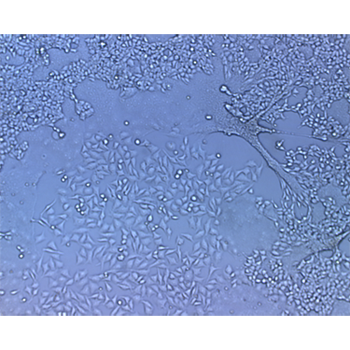

ELISPOT-β galactosidase readout assay to quantify HIV titers and neutralizing antibody titers